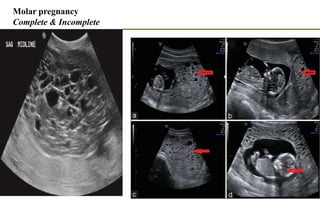

Molar pregnancy

Complete & Incomplete